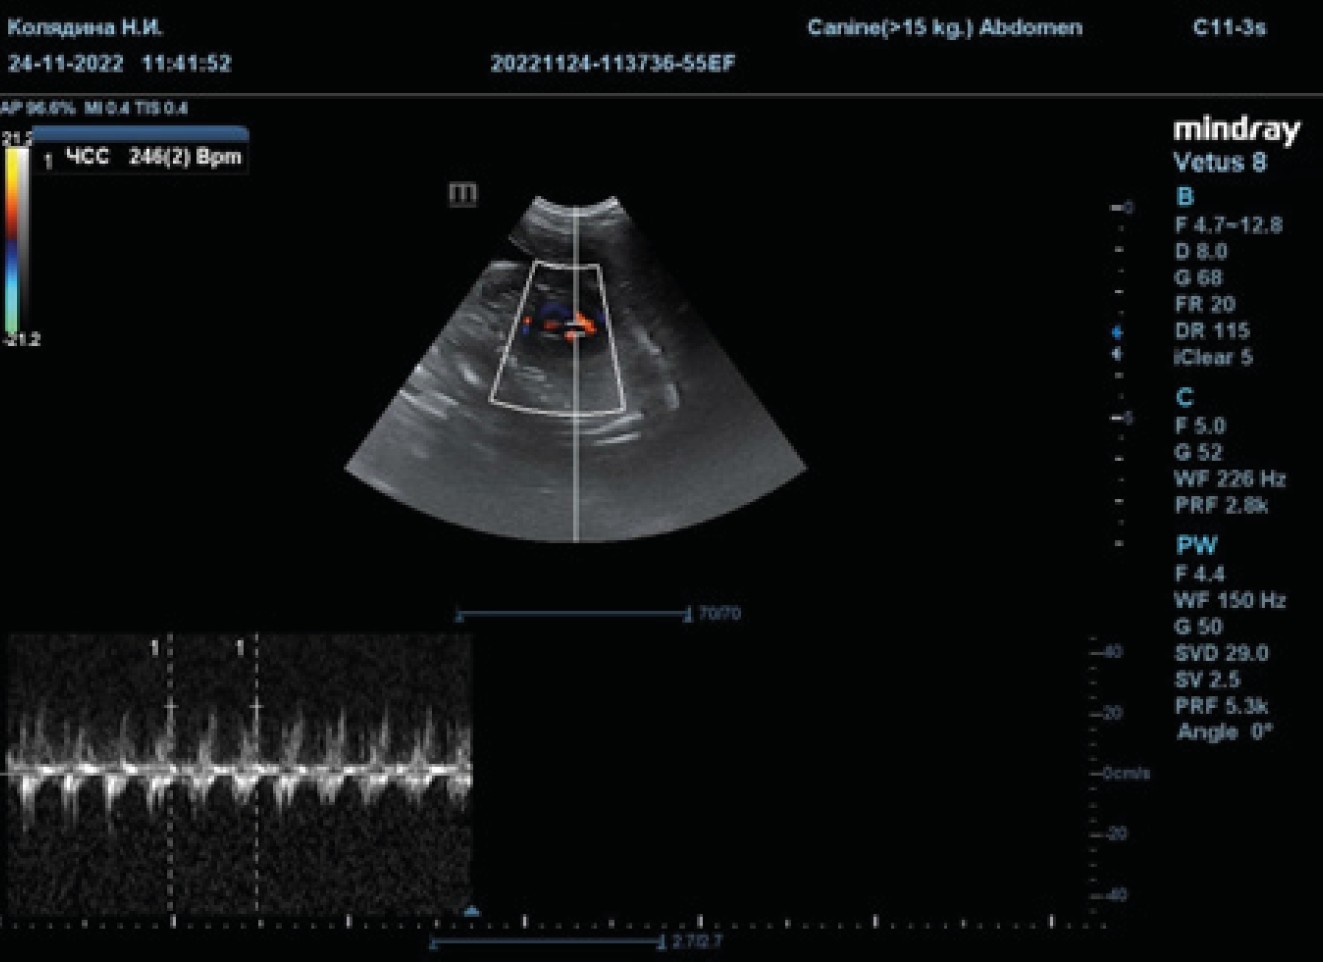

Fig. 2. The method of fetal heart rate monitoring

Source: compiled by N.I. Kolyadina, A.V. Shumeyko on the Mindray Vetus 8 Ultrasound Machine.

Source: compiled by N.I. Kolyadina, A.V. Shumeyko on the Mindray Vetus 8 Ultrasound Machine